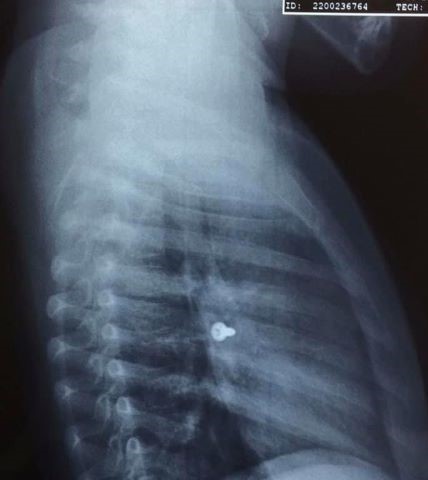

Σύμφωνα με τα όσα έκανε γνωστά ο αναπληρωτής καθηγητής ΩΡΛ της Ιατρικής Σχολής Κρήτης, Μανώλης Προκοπάκης, το κοριτσάκι μεταφέρθηκε στο νοσοκομείο και αμέσως του έγιναν ακτινογραφίες που έδειξαν πού βρισκόταν η βίδα.

Οι γιατροί άμεσα οδήγησαν τo τρίχρονο παιδί στο χειρουργείο και μετά από αρκετή ώρα κατάφεραν να αφαιρέσουν την βίδα. Ο κ. Προκοπάκης σε ανάρτησή του στα social media ανέφερε: «Πολύ επείγον χειρουργείο! Πριν από λίγο. Αφαίρεση βίδας από αριστερό βρογχικό δέντρο τρίχρονου κοριτσιού. Πολύ επικίνδυνο…».